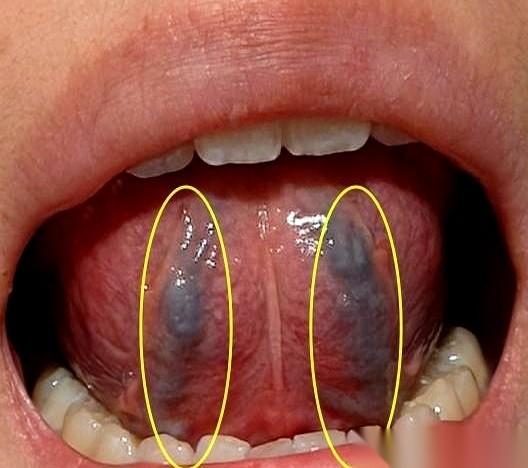

最扎心的是什么? 不是身体虚,是花了大价钱去补,结果全补了个寂寞。 感觉自己像个漏气的轮胎,怎么打气都鼓不起来。 我跟你讲,你伸出舌头看看。 要是舌头又干又燥,跟好几天没下雨的地似的;舌头底下那两条筋,颜色发紫发黑…… 恭喜你,大概率跟我之前一样,方向全搞反了。 你以为是身体缺“燃料”? 错。 你身体里可能是一片沼泽地,路都给淹了。 你花大钱买的那些“高级养料”,什么人参、鹿茸、海参……浩浩荡荡运过来,结果呢?快递车全陷在泥里,压根儿送不到“发动机”那里去。 营养进不去,垃圾出不来。 全堵在身体里,成了又湿又浊的“垃圾”。 所以你还是老样子:脑子像一团浆糊,转不动;头发大把大把地掉;稍微动一下就喘,累得像跑了十公里;腰酸得直不起来,更别提夫妻之间那点事儿了,有心无力,自己都觉得扫兴。 补了,又好像没补。钱花了,罪受了,人还是蔫的。 懂了吗? 得先“排涝”,把沼泽地的水抽干,把路修好。 路通了,再送养料进去,才能真正把根给养回来。 别再傻乎乎地当冤大头了。进补之前,先看看你家的路,到底堵没堵。